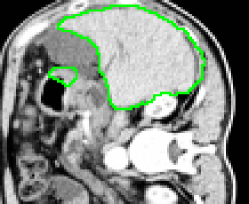

4.1 Metrication artifacts and minimal surfaces

We begin by comparing the CCMF segmentation result with the classical max-flow algorithm (graph cuts). Figure 3 shows the segmentation of a brain, in which the contours obtained by graph cuts are noticeably blocky in the areas of weak gradient, while the contours obtained by both AT-CMF and CCMF are smooth.